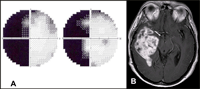

Figura 2. Una paciente de 42 años refirió molestias visuales inespecíficas y dificultades para deambular en las últimas semanas. Dos años atrás se practicó una biopsia estereotáctica para estudiar una lesión intracraneal, compatible con meningioma. Figura 2A. Campo visual. Hemianopsia homónima izquierda. Figura 2B. Resonancia magnética cerebral T1 con gadolinio. Corte axial: Lesión de grandes dimensiones en el lóbulo temporal derecho que desplaza las estructuras de la línea media y comprime la cintilla óptica derecha (flecha).

Figura 3. Un joven de 32 años consultó por visión borrosa en el ojo derecho. Tenía antecedentes de adenocarcinoma pleuro-pulmonar y mediastínico con metástasis cervicales activo por lo cual recibía quimioterapia (cisplatino+docitaxel) y radioterapia, El examen del fondo de ojo inicial no mostró alteraciones iniciales, y la campimetría (A). reveló un patrón que sugería una hemianopsia homónima incongruente. El estudio de neuro-imagen no mostró anomalías que comprometieran la vía óptica retroquiasmática. Fondo de ojo (B) En el siguiente control se detectaron lesiones en la coroides de ambos ojos que remedaban el patrón de hemianopsia homónima.